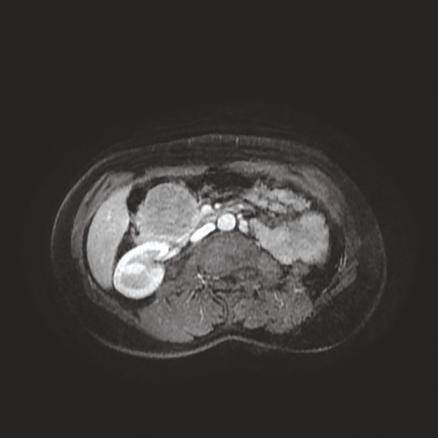

Cette femme de 38 ans était admise aux urgences pour des épigastralgies sans antécédent pathologique notable, avec une fièvre à 38,6 °C ; le bilan biologique mettait en évidence un syndrome inflammatoire sans perturbation du bilan hépatique. La tomodensitométrie abdomino-pelvienne sans et avec contraste réalisée (fig. 1 ) montrait une masse de la tête du pancréas, bien limitée, de 65 x 60 mm, isodense, réhaussée de façon hétérogène, délimitant des zones hypodenses. L’imagerie par résonance magnétique (IRM) pancréatique objectivait une masse de la tête du pancréas en isosignal T1, signal intermédiaire T2, de rehaussement périphérique délimitant une zone centrale liquidienne (fig. 2 ). Une duodéno-pancréatectomie céphalique était réalisée, permettant le diagnostic histologique de tumeur pseudopapillaire et solide du pancréas.